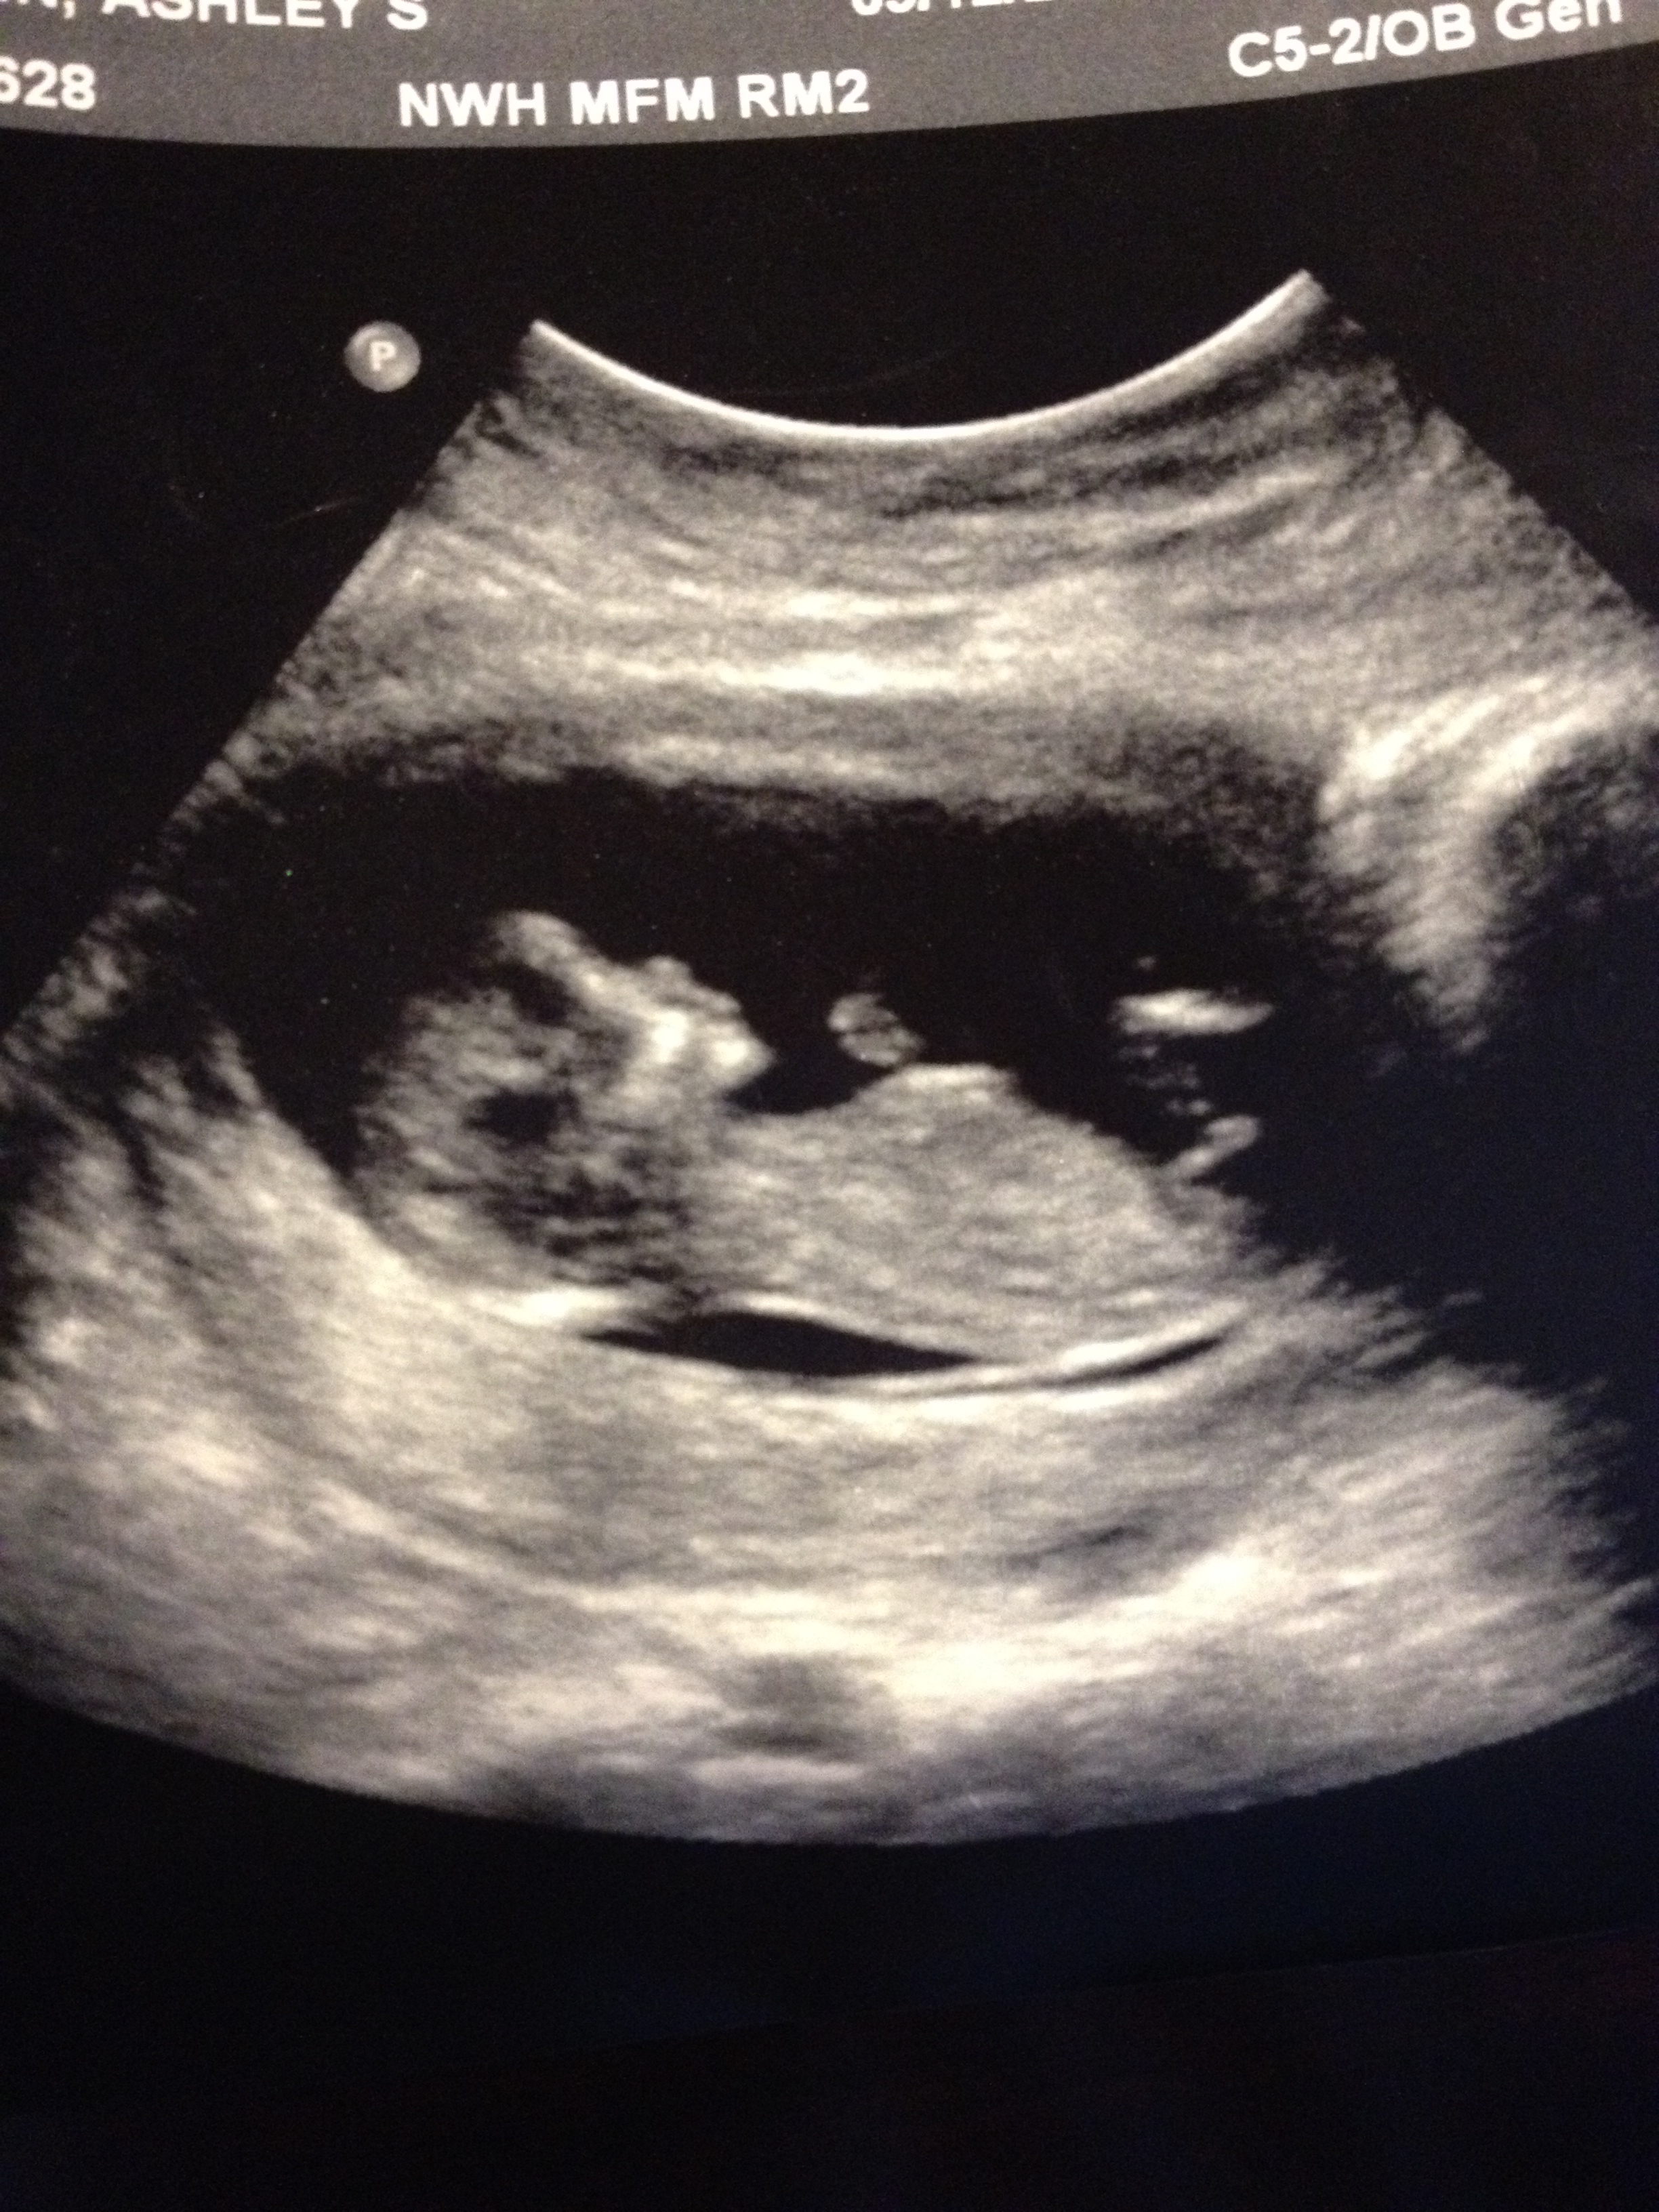

Check out ds3 nub shot! If this doesn't SCREAM BOY then I don't know what does.

Praying nothing is so obviously sticking up next week at my 12 week scan with #4...